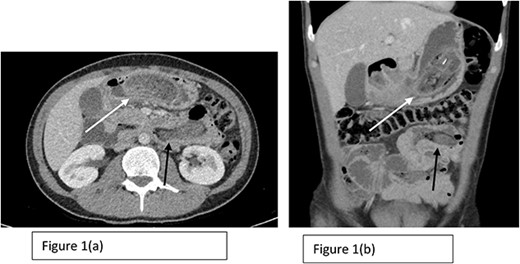

A CT scan of the abdomen and pelvis was performed showing multiple large foreign bodies in the stomach and proximal small bowel (as seen in Fig. 1), with a differential diagnosis of bezoars. Given these findings, the history was revisited and the patient was asked if he had consumed anything unusual. The patient admitted to habitually consuming his own hair as a response to stress for at least 20 years prior to presentation.

Axial (a) and coronal (b) sections of CT scan showing the presence of Trichobezoar in the stomach with extension into the small bowel (The white arrow in both Fig. 1a and b shows the trichobezoar in the stomach while the back arrow shows the extension into the small bowel with surrounding inflammation).